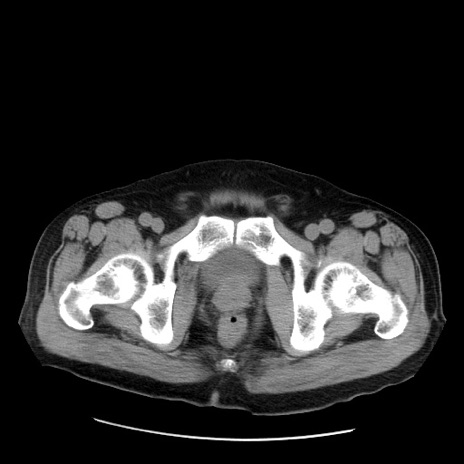

症例20(横断像)

【症例】 60歳代男性

【主訴】 腹部膨満、嘔吐

【現病歴】5日前頃より倦怠感を認め食事量減少し4日前の朝嘔吐、食事摂取困難となった。 3日前近医受診し点滴施行され整腸剤などを処方された。 当日他院を受診し、腹部膨満著明、炎症反応の上昇(CRP10.8、WBC11200)あり、紹介受診となる。

【身体所見】 意識JCS1 受け答えがはっきりしないBP 111/57mHg、 P 67bpm、、BT35.2°C、SpO2 97%(RA)、 腹部:膨隆、打診で鼓音あり、全体的に圧痛有り、腸蠕動音(-)、反跳痛ははっきりせず。

【データ】WBC 11400、CRP 14.20